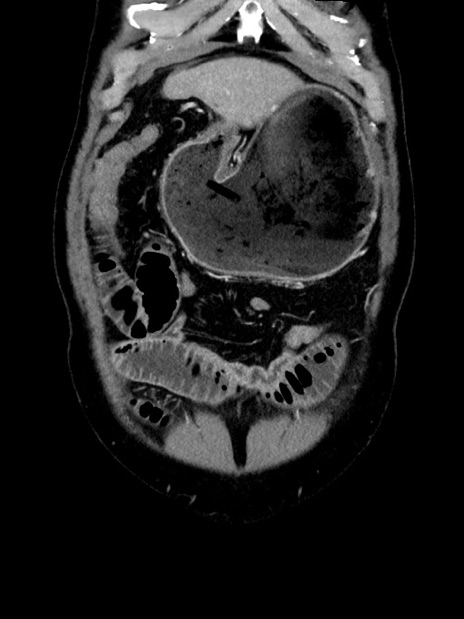

症例35(冠状断像)

【症例】70歳代 男性

【主訴】腹部膨満、嘔吐

【現病歴】昨日より腹部膨満感出現。本日増悪し、仙痛出現。嘔吐あり、受診。

【既往歴】糖尿病、胆摘後

【身体所見】BP 149/80mmHg、HR 74/min、BT 35.9℃、腹部:膨満、軟、圧痛なし。腸雑音減弱あり。上腹部正中切開瘢痕あり。

【データ】WBC 13500、CRP 1.72